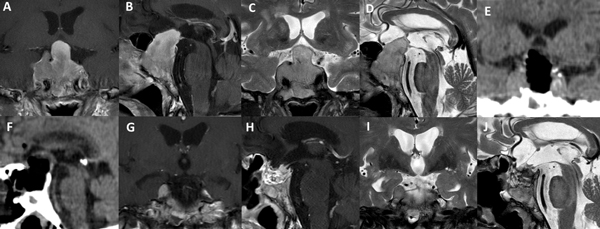

Figura 5. Paciente de 45 años con prolactinoma infradiafragmático resistente a cabergolina. Se utilizó un abordaje de Guante Blanco para su tratamiento. A-D: RM preoperatoria. E-F: TC del primer día postoperatorio. G-J: RM postoperatoria.

Figura 6. Paciente de 62 años, acromegálica, con adenoma gigante Hardy C y Knosp 4. No fue candidata a abordaje de Guante Blanco. Se utilizó un abordaje extendido para su tratamiento. A-D: RM preoperatoria. E-F: TC del primer día postoperatorio. G-J: RM postoperatoria.